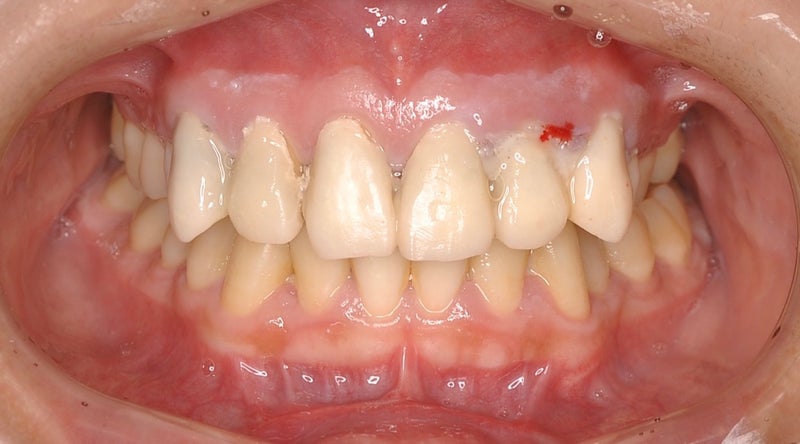

<当院で新製した仮歯装着時の状態・正面>

▶︎1回の無痛リラクゼーション治療で痛みも全て治まり、ひとまずの仮歯も元の物より綺麗になりました。